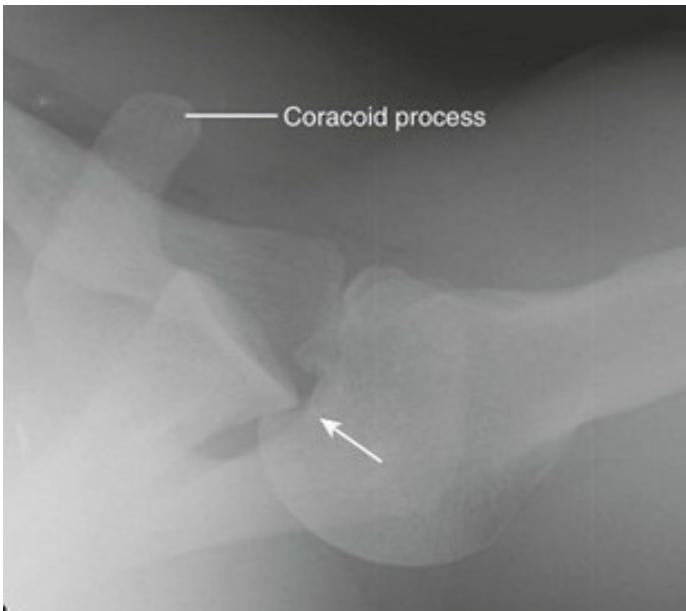

Imaging

Questions for analysis:

- What are the two findings in recurrent shoulder dislocation?

- What do you see on the images?